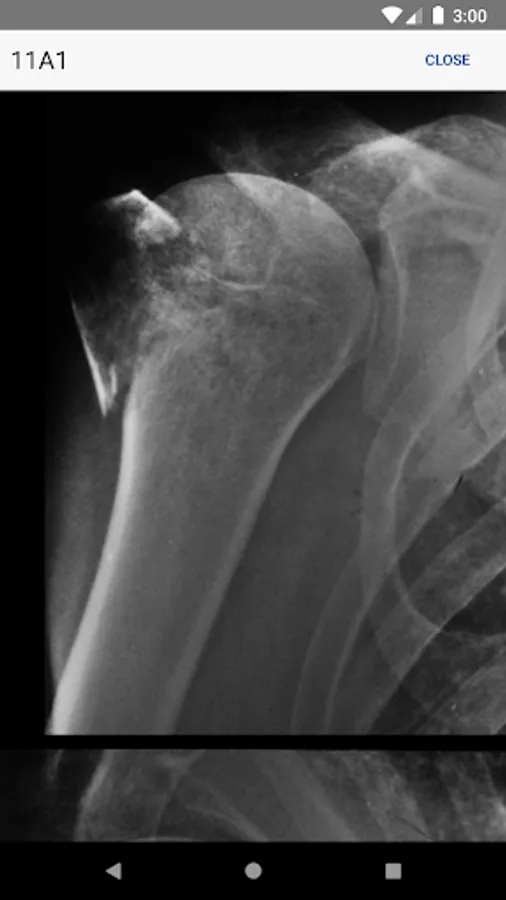

• Information regarding radiological investigations used for classifying a specific fracture

• High-quality, enlargeable x-rays are included